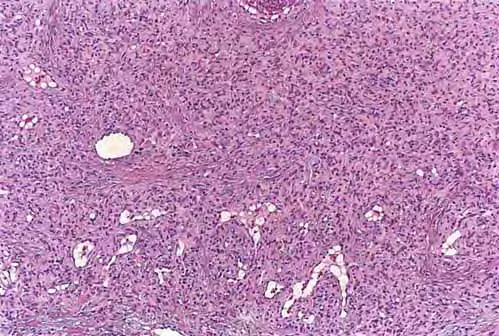

Epithelioid hemangioendothelioma =ورم بطانة الاوعية البشرواني